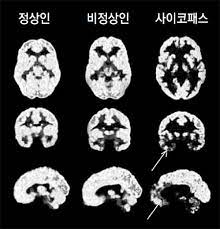

연구 결과에 따르면 사이코패스 환자들은 감정을 지배하는 전두엽의 기능이 일반인의 15% 밖에 되지 않는다. 그래서 다른 사람의 고통에 무감각하고 양심의 가책을 느끼지도 않는다. 고통에 무감각하기 때문에 저지른 죄를 인지하지 못하고, 처벌을 두려워하지 않는다.